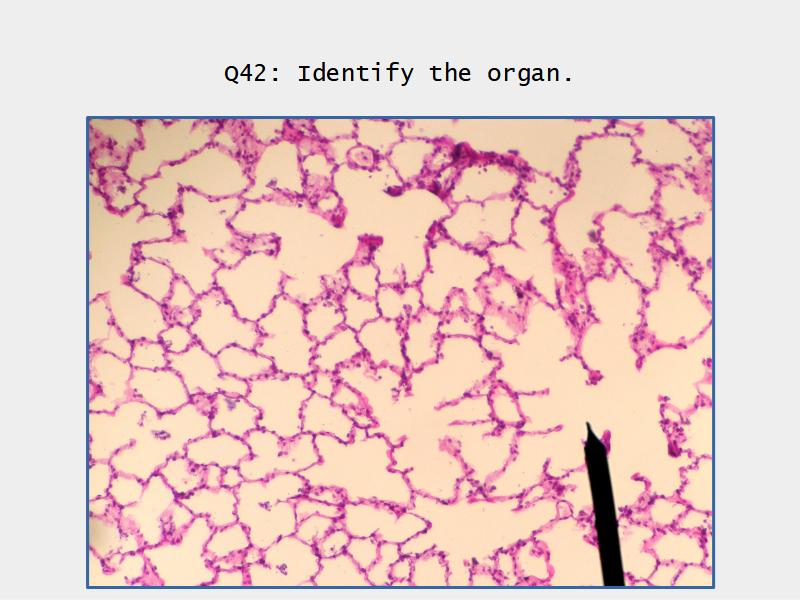

- Slide 72 & 74: Lung

- Alveoli

Lungs